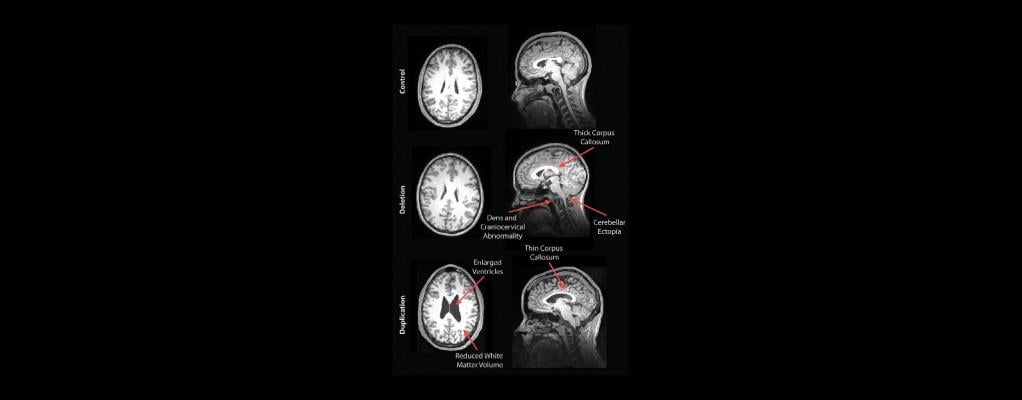

Example images for a control participant , a deletion carrier, and a duplication carrier. In the sagittal image of the deletion carrier, the thick corpus callosum, dens and craniocervical abnormality, and cerebellar ectopia are shown. For the duplication carrier, the sagittal image shows the thin corpus callosum and the axial image shows the increased ventricle size and decreased white matter volume. Image courtesy of the Radiological Society of North America (RSNA).

The participants completed a battery of cognitive and behavioral tests, and neuroradiologists reviewed the brain images for development-related abnormalities. The results showed some striking differences in the brain structures of deletion and duplication carriers compared with non-carriers. For instance, the corpus callosum — the fiber bundle that connects the left and right sides of the brain — was abnormally shaped and thicker in the deletion carriers but thinner in the duplication carriers, compared to the control group and familial non-carriers.

Other stark differences were apparent. The deletion carriers displayed features of brain overgrowth, including the extension of the cerebellum, the bottom back part of the brain, toward the spinal cord.

The duplication carriers showed characteristics of brain undergrowth, such as decreased white matter volume and larger ventricles — the cavities in the brain filled with cerebrospinal fluid.